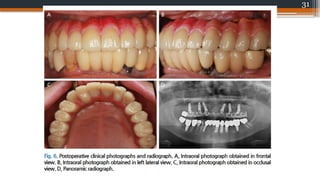

31